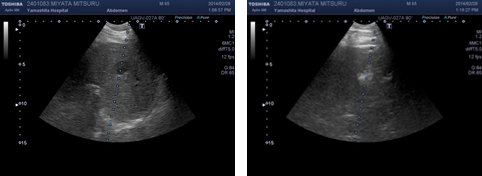

RFA(ラジオ波焼灼術)

肝臓癌に対して、その患部をラジオ波を用いて焼いて治療する方法です。